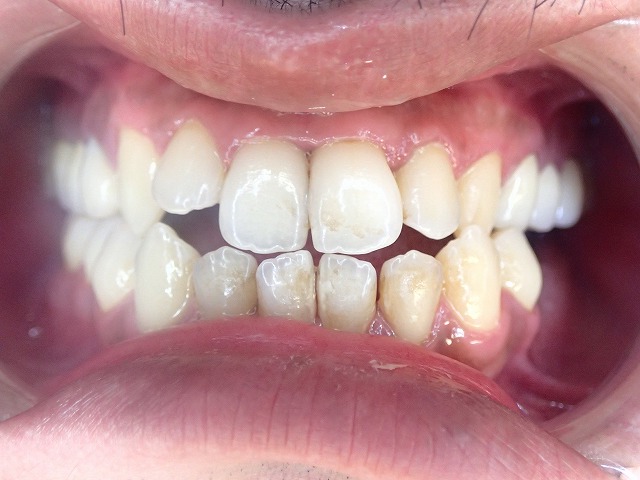

治療途中での転院です。都内でかなり高価な見積もりだったのと

予約が取りにくい ということで転院とのことです。

治療途中で転院する場合は、見た目を整える前に、

今の歯がどの状態にあるかを正確に把握することが大切です。

このページでは、スクリューピンが入った歯や根管治療途中の歯、歯冠破折した歯を、

リスク説明のうえでジルコニア修復へ進めた経過を紹介しています。

治療途中での転院です。理由は治療費用の問題です。都内で1本18万円は相場です。

治療途中の転院は、責任問題などのリスクを承諾の上で処置開始

すべて、やりっぱ で来院

左上 一本スクリューピン 2本根管処置中

左側、一本はスクリューピンが入っており、2本は根管治療の途中です。